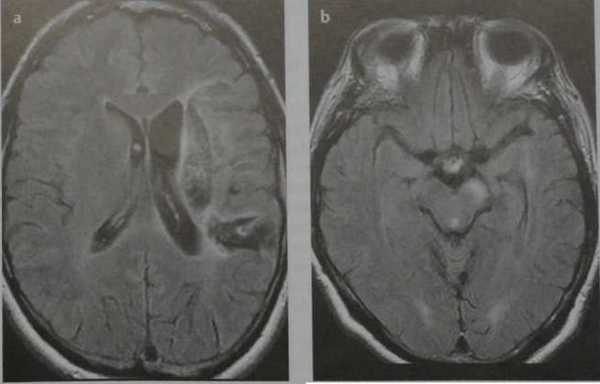

Внутримозговая гематома (граница острой и ранней подострой стадий - 3 суток), осложнившаяся внутрижелудочковым кровоизлиянием.

Внутримозговая гематома, поздний подострый период (14-21 день) с перифокальным отеком вокруг гематомы.

Внутримозговая гематома правой теменной доли. Граница поздней подострой и ранней хронической стадии. В Т2-ВИ виден ободок гемосидерина (стрелка).

Хочется подчеркнуть возможность МРТ в выявлении последствий геморрагического поражения - остается хорошо дифференцируемый по Т2 ободок гемосидерина, недоступный для визуализации при других методах нейровизуализации.

Стрелками показан ободок гемосидерина по периферии постишемической кисты.